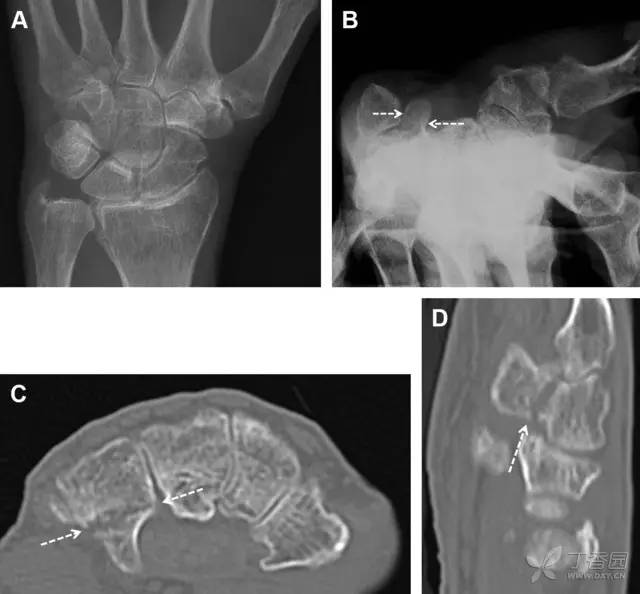

腕掌关节骨折脱位为高能量损伤,常伴有神经损伤。腕掌关节组成骨多,侧位片上重叠遮挡多,骨折不易发现,容易漏诊。在前后位片上,关节面不平滑、关节间隙不对称、关节皮质破坏、关节面重叠常提示腕掌关节骨折脱位。特别是第 4、5 腕掌关节脱位,在前后位片上不容易发现;该损伤不稳定,也称为「变异型拳击手损伤/骨折」。

图 4 第 4、5 腕掌关节骨折脱位。(A)正常腕掌关节,关节面平衡起伏、平行;前后位(B)、斜位(C)、侧位(D),第 5 掌骨近端附近软组织肿胀(白色箭头),冠状面关节面重叠,背侧撞击剪切应力致钩状骨骨折(*),在前后位及斜位片上可见双密度影。第 4 掌骨底部可见微小骨折碎片(D,虚线箭头),第 4、5 掌骨掌侧成角。(E~G)变异型拳击手损伤:第 4、5 掌骨背侧脱位而未见骨折(E,虚线方框),钩状骨有骨折小碎片(F,短虚线箭头),第 4 掌骨基底部关节内骨折(G,长虚线箭头)